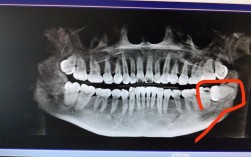

- X光片(全景片、头颅侧位片、必要时CBCT)

- 智齿的位置、形态、萌出方向、与邻牙/神经管的关系